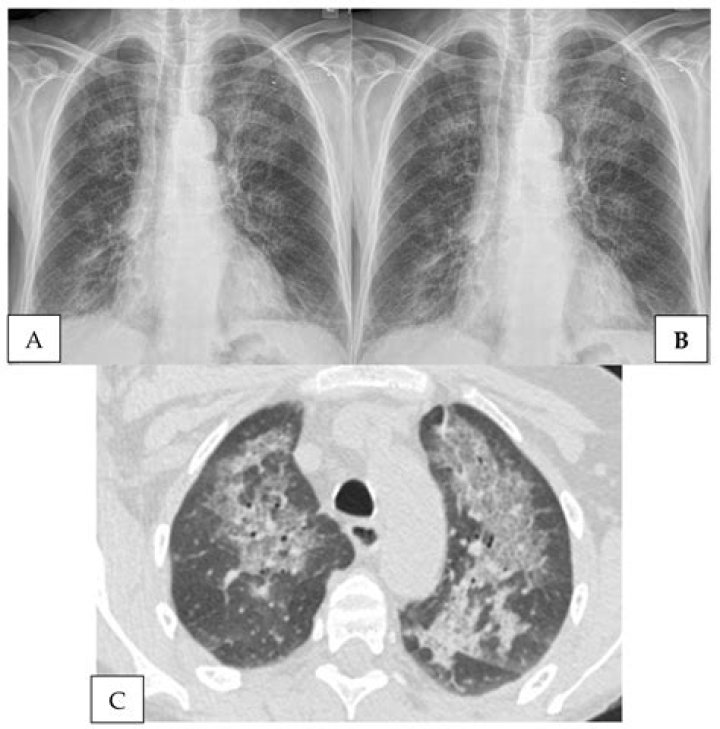

Diagnosing pneumonia typically involves a physical exam, chest X-rays, and blood tests. Once diagnosed, treatment depends on the type and severity of the infection.